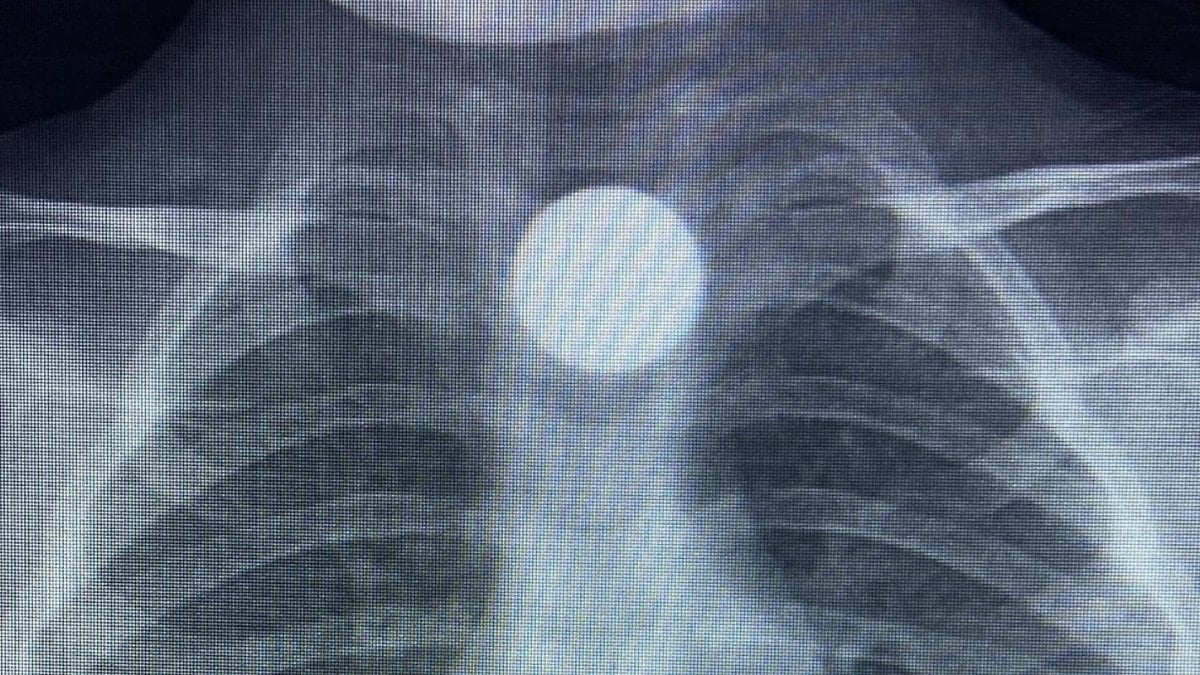

Çocuğun parayı yuttuğunu fark eden ailesi, Bilal K.’yi vakit kaybetmeden özel araçla İnegöl Devlet Hastanesi’ne götürdü. Hastanede yapılan muayene ve görüntüleme işlemlerinde, madeni paranın çocuğun yemek borusunda takılı kaldığı tespit edildi.

İlk müdahalesi İnegöl Devlet Hastanesi’nde yapılan Bilal K., ileri tetkik ve tedavi amacıyla ambulansla Bursa Yüksek İhtisas Eğitim ve Araştırma Hastanesi’ne sevk edildi.